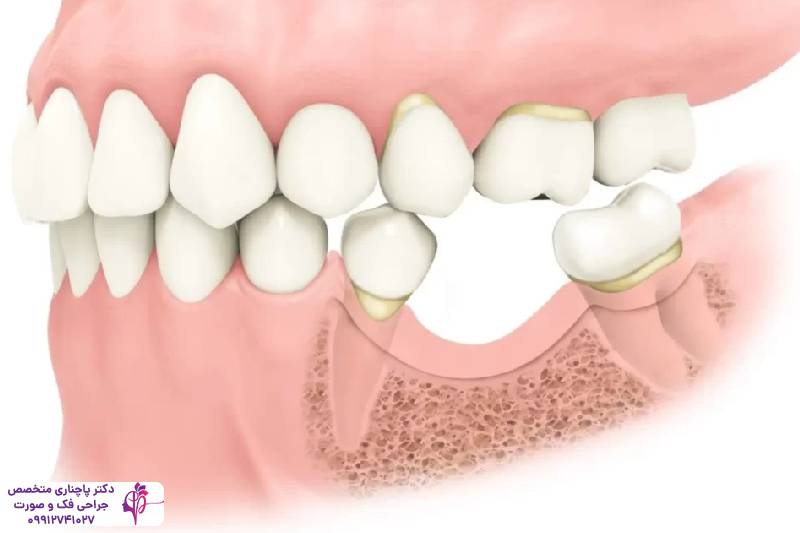

قبل از اینکه با علائم و روش درمان تحلیل استخوان فک آشنا شویم بیایید ببینیم دقیقا منظور از تحلیل استخوان فک چیست. وقتی بافت استخوانی کاهش پیدا میکند و حجم و تراکم خود را از دست میدهد و ضعیف میشود در واقع تحلیل استخوام فک اتفاق افتاده است. استخوان فک که دندانها را در جای خود نگه میدارد مثل یک ستون برای ساختار صورت عمل میکند. در حالت عادی استخوان فک در یک چرخه طبیعی مدام بازسازی میشود. در این چرخه سلولهای استئوکلاست استخوان قتدیمی را تجزیه میکنند و سلولهای استئوبلاست استخوان جدید میسازند. وقتی این تعادل به هم میخورد استخوان تراکم خود را به تدریج از دست میدهد. یکی از مهمترین دلایل به هم خوردن این تعادل افتادن دندانهاست، وقتی دندانی در استخوان فک وجود ندارد عملا نیرویی برای جویدن اعمال نمیشود و بدن استخوان فک را یک ناحیه غیرضروری تلقی میکند و کاری هم برای تقویت آن انجام نمیدهد.

کم شدن تراکم بافت استخوانی دلایل داخلی و خارجی مختلفی دارد. این دلایل تعادل طبیعی بدن در بازسازی استخوان را به هم میزند. از دست رفتن دندان شایعترین علت این مشکل است. ریشههای دندانها یکی از عوامل محکم شدن استخوان فک هستند وقتی ریشهای در استخوان وجود نداشته باشد عملا استخوان آن ناحیه تحریک نمیشود و بدن به تدریج استخوان آن قسمت را جذب میکند. بیماریهای لثه مثل پریودنتیت نیز از جمله مواردی هستند که منجر به بروز علائم تحلیل استخوان فک میشود. در اثر این بیماریها باکتریهای موجود در پلاک دندانی به بافت لثه و استخوان زیرش حمله میکنند و کم کم آن را از بین میبرند. مشکلات سینوسی هم میتواند روی تحلیل استخوان فک بالا تاثیر داشته باشد. چون فشار سینوسها بعد از کشیدن دندانهای مولر میتواند روند تحلیل استخوان را سریعتر کند. ناهماهنگی دندانها هم یک عامل دیگر این مشکل است. این ناهماهنگیها توزیع نیروی جویدن را نامتوازن میکند و آن بخشهایی که کمتر در اثر جویدن تحریک میشوند کمکم تحلیل میروند.

ایمپلنت دندان یکی از موثرترین روشها برای درمان تحلیل استخوان فک و جلوگیری از پیشروی آن است. پایههای تیتانیومی ایمپلنت مثل ریشه دندان طبیعی عمل میکند و با تحریک بافت استخوان جلوی تحلیل رفتن آن را میگیرد. گرچه کاشت ایمپلنت به یک بستر قوی و مناسب نیاز دارد و در صورتی که استخوان فک تراکم خود را از دست داده باشد باید با درمانهای جانبی مثل پیوند استخوان بستر مناسب برای کاشت ایمپلنت را آماده کرد.